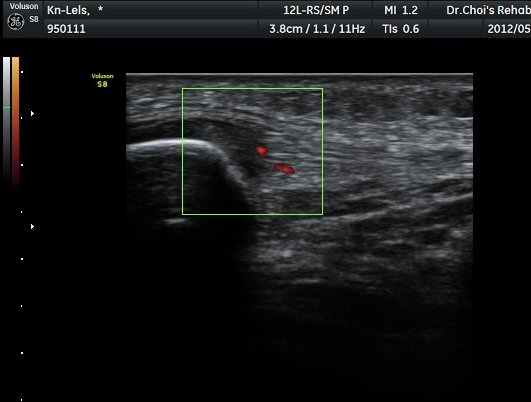

½½°³°ñ¾Æ·¡ ÈûÁÙ Á¾´Ü¸é°Ë»ç¿Í Ⱦ´Ü¸é°Ë»ç¿¡¼­ ÈûÁÙÀÇ ºñÈİ¡ °üÂûµÇ°í(±×¸² 3, 4).

ÈûÁÙÀÇ ºñÈÄ´Â °ÇÃø(±×¸² 5)°ú ºñ±³ÇÏ¸é ¶Ñ·ÈÇϰí, ÆÄ¿öµµÇ÷¯°Ë»ç¿¡¼­ ÈûÁÙ³»¿¡

Ç÷·ùÁõ°¡µµ È®ÀδϵȴÙ(±×¸² 6, 7).